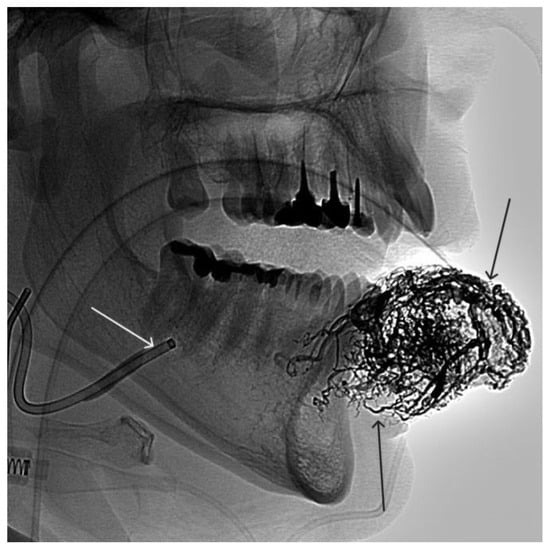

A 35-year-old male patient was admitted to the clinic with complaints of a cosmetic defect in the lower lip area. He has been ill since birth; 18 years ago he was diagnosed with AVM of the lower lip and microsurgical removal was performed. Over the past three years, the growth of formation has been noted. Angiography revealed a relapse of arteriovenous malformation with afferents from the left facial artery (Figure 3). In three years, he underwent several stages of treatment: endovascular embolization with gelatin sponge and embolization with pure ethanol, without effect. The patient underwent endovascular embolization of the AVM of the lower lip with 5 mL of non-adhesive composition ONYX18. Arteriovenous malformation was shut down totally (Figure 4, Figure 5 and Figure 6). The patient was directed to the next stage of surgical treatment—AVM removal by cosmetic surgeons (Figure 7). The mRs score at discharge was 1.

Figure 4. The process of introducing ONYX18 into the AVM of the lower lip (the white arrow indicates the microcatheter, the black arrow indicates the spread of embolizate along the vascular network of the formation).

Figure 5. X-ray in single shot mode. The NAGLEMs cast is visualized, filling the vascular network (the white arrow indicates the guiding catheter at the ostium of the left facial artery, the black arrow indicates the cast).